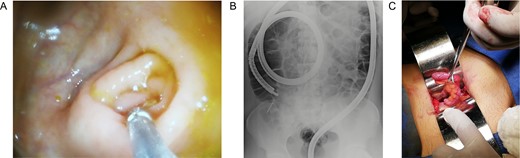

In this context, a surgical approach was needed to assess the appendix and the cecum wall. After a Rocky-Davis incision, the appendix was exposed and an object of hard consistency was found at its tip (Fig. 3B). The surgical decision was straightforward, the appendix was resected, and the surgery was completed without complications (Fig. 1C).

After this, the appendix was dissected and a 30 mm nail was found inside its lumen (Fig. 2C and Supplementary Video).

(A) Completely resected appendix. (B) Appendix and metallic nail.